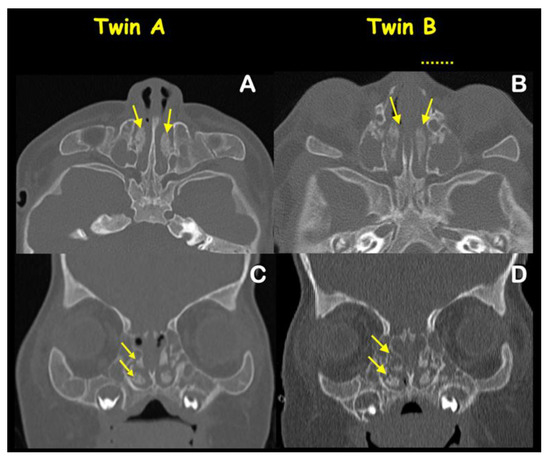

2. Patient Report

4.3. Malformation of Middle Ear and Hearing Loss

4.4. Dehiscence of Posterior Semicircular Canals